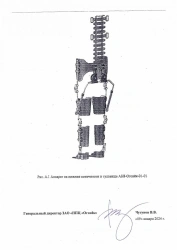

Lower Limb and Torso Apparatus with Reciprocal Gait System

US$1,800-7,200

Angle of flexion at the knee joint:

90...30

Material:

Leather, textile, thermoplastic, laminated plastic, carbon plastic

ANNAVEA LLC 🇷🇺